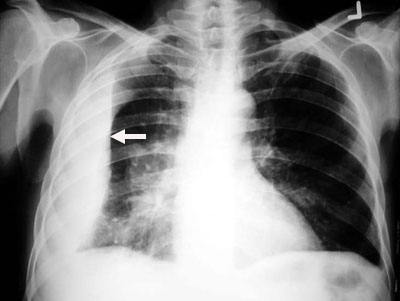

• Note pleural effusion on left (yellow arrow) in the adjacent CXR.

• Upper margin high in axilla in PA view (yellow arrows)

• Loss of silhouette. In the images below note lack of identifiable left diaphragm before and visible diaphragm after clearance of fluid (Silhouette sign principle)

Before  thoracentesis

Left diaphragm is not identifiable

After thoracentesis

Left diaphragm is seen clearly.